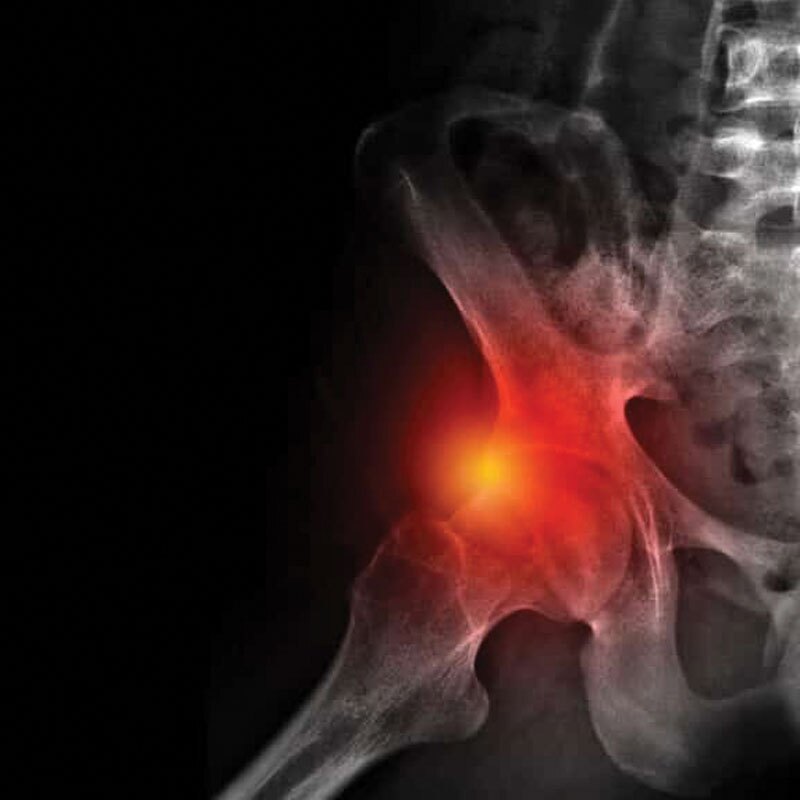

Femoroacetabular Impingement (FAI) – Symptoms, Causes, and Treatment Options

Femoroacetabular impingement (FAI) happens when the ball (femoral head) and socket (acetabulum) of your hip joint do not fit together properly. This mismatch causes extra friction during movement, which can damage the cartilage and labrum (the soft tissue ring around the hip socket). Over time, this damage may lead to hip arthritis.

- Cam impingement: The ball of the hip is not perfectly round, causing it to jam against the socket.

- Pincer impingement: The socket covers too much of the ball, creating pinching during movement.

- Combined impingement: Both cam and pincer changes are present.